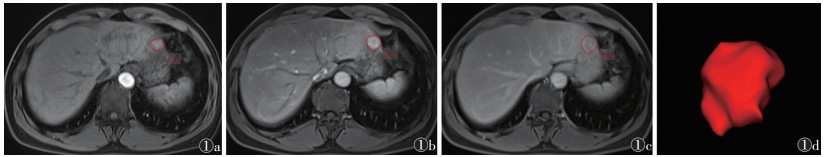

1.5 图像分割与特征提取在Radcloud平台(版本3.1.0)上,采用双盲法标注数据,由1位具有3年MRI读片经验的腹部影像诊断医师在MRI图像上逐层勾画病灶边缘,再由1位具有10年MRI读片经验的腹部影像诊断医师检查所有轮廓,并保存ROI(图 1)。分别从AP、VP、DP及AP+VP+DP图像的ROI中提取影像组学特征。

| 注:图 1a~1c分别为动脉期、门静脉期、延迟期沿病灶边缘勾画ROI,图 1d为病灶分割图 图 1 肝细胞癌ROI勾画示意图 |